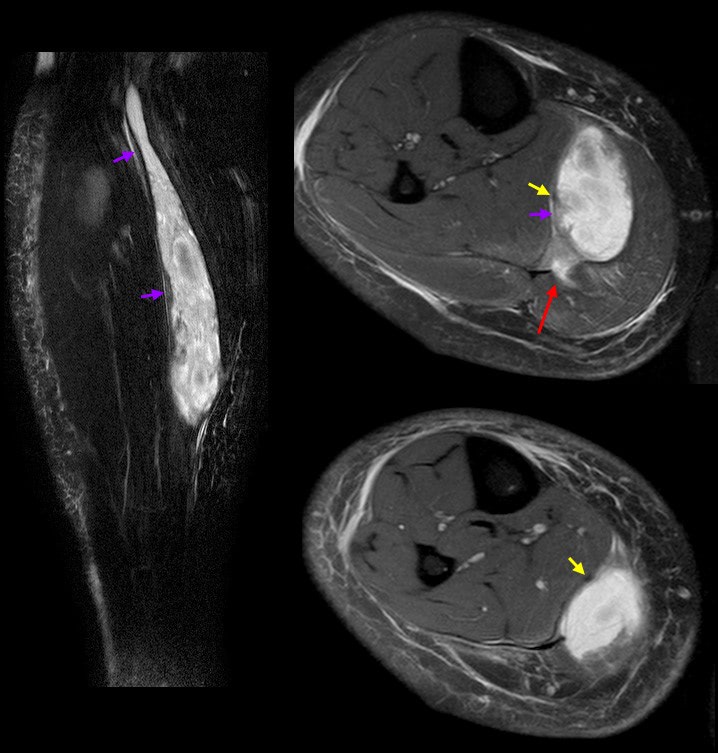

Although the diagnosis of a calf strain can often be made through a clinical examination, imaging can be useful to confirm the location and severity of the injury. However, in most cases, imaging won't be necessary unless the recovery is slow or stalled.

Musculoskeletal ultrasound and magnetic resonance imaging (MRI) are good choices for imaging calf strains. MRI can provide a more detailed view of the injury, including surrounding tissue damage, and can help to evaluate the healing process. Ultrasound is cheaper, more accessible, and faster, and can provide information about the presence of blood clots or other complications. However, there are no specific guidelines for using ultrasound to determine when it is safe to return to sports activities. This is because imaging doesn't determine the level of function you have.